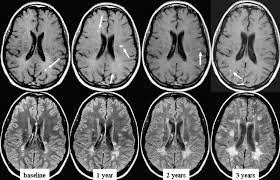

Multiple lesions in different regions of the brain) but also in time. Tumefactive multiple sclerosis is a term used to describe patients with established multiple sclerosis who develop large aggressive demyelinating lesions, similar/identical in appearance to those seen in sporadic tumefactive demyelinating lesions (tdl).tdl is now considered to be a separate entity, lying on a spectrum between multiple sclerosis and postinfectious demyelination/acute. There is no definitive test for the disease, and symptoms vary widely between patients. Mri and ms multiple sclerosis (ms) is a condition in which the body's immune system attacks the protective covering (myelin) surrounding the nerves of the central nervous system (cns). 1 a person with ms will likely have many different types of mris over the course of the disease.

These demyelinating lesions may sometimes mimic brain tumors because of the associated edema and inflammation. Multiple sclerosis (ms) is a common central nervous system (cns) disease characterised pathologically by the development of multifocal inflammatory demyelinating white matter lesions. 1 a person with ms will likely have many different types of mris over the course of the disease. The cns includes the brain, spinal cord, and optic nerves. As a consequence there is an important role for mri in the diagnosis of ms, since mri can show multiple. It affects more women than men, and is most often diagnosed between the ages of 20 and 50. Conventional magnetic resonance imaging (mri) has routinely been used to improve the accuracy of multiple sclerosis (ms) diagnosis and prognosis. Multiple sclerosis (ms) is the most common inflammatory. To describe the factors that are associated with gadolinium enhancement on mri in patients with multiple sclerosis (ms) and symptoms of relapse. Multiple lesions in different regions of the brain) but also in time. Optic nerve evaluation within normal limits. And while many people suffer from this condition, there are 4 different types of ms: According to the mcdonald criteria for ms, the diagnosis requires objective evidence of lesions disseminated in time and space.

1 a person with ms will likely have many different types of mris over the course of the disease esclerosis multiple. Topic overview an mri scan is the best way to locate multiple sclerosis (ms) lesions (also called plaques) in the brain or spinal cord.